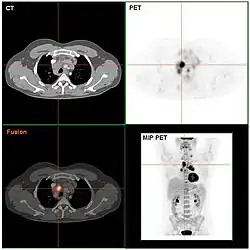

Das Ziel der folgenden klinischen Stadienbestimmung (klinisches Staging) ist es, alle Manifestationen zu erfassen und die Ausbreitung der Krankheit zu bestimmen. Das geschieht anhand der Befunde von Anamnese, Untersuchung, Laborwerten, Biopsien des Knochenmarks mit feingeweblicher Beurteilung sowie bildgebender Verfahren. Dazu gehören Röntgenbilder des Thorax in zwei Ebenen, Thorax-Computertomografie (CT), Sonografie (Ultraschall) und CT des Abdomens und eine Knochenmarkspunktion. Anstelle des CT kann bei bestimmten Patientengruppen mit Morbus Hodgkin auch die Magnetresonanztomographie (MRT) zum Einsatz kommen. Die Positronen-Emissions-Tomografie (PET) wird im Staging des Morbus Hodgkin zunehmend dann zusätzlich zur CT oder MRT eingesetzt, wenn die anderen vorgenannten bildgebenden Verfahren keinen ausreichend sicheren Aufschluss über einen Rückgang der Erkrankung unter Behandlung bieten. Ziel der PET-Untersuchungen soll sein, die Therapie noch besser nach der Erkrankungsaktivität zu steuern.

Darüber hinaus ist der Zusammenhang zwischen Strahlentherapie des Hodgkin-Lymphoms und der Entstehung von Sekundärmalignomen (Zweitkrebserkrankung) gut beschrieben und mittlerweile etabliert. Die Häufigkeit oder Wahrscheinlichkeit, dass Zweitmalignome auftreten, hängt einerseits von der verwendeten Dosis und andererseits vom Bestrahlungsfeld und dessen Größe ab. Folgerichtig ist es Ziel von Therapieweiterentwicklungen, die Bestrahlung auf das unumgängliche Maß zu reduzieren. Eine Dosisabsenkung unter 20 Gy Gesamtdosis ist nicht sinnvoll, da bei einer solchen Dosis die Wirksamkeit der Bestrahlung gegen das Hodgkin-Lymphom eingeschränkt wird. Ein Ansatz verfolgt die Reduktion der Bestrahlungsfelder. Einerseits kann durch Intensivierung oder neue Chemotherapien die Notwendigkeit einer Bestrahlung vermindert werden. Zum anderen können unter Chemotherapie vollständig zurückgebildete befallene Regionen von der Bestrahlung ausgenommen werden. Um möglichst die therapeutischen Effektivität der Gesamtbehandlung nicht zu vermindern, werden zur Feststellung der Bestrahlungsnotwendigkeit Untersuchungsverfahren wie das PET eingesetzt.

Eine Möglichkeit der Erfolgskontrolle der Therapie kann die Positronen-Emissions-Tomographie (PET) zum Beispiel nach dem zweiten Chemotherapiezyklus sein. Bei dem Vergleich von PET-negativen (= gute Prognose) und PET-positiven (= schlechte Prognose) Patienten erhielten Aldin und seine Mitarbeiter die folgenden Ergebnisse: Die Evidenz ist sehr ungewiss bezüglich der Wirkung des Effekts von negativen und positiven interimsmäßig durchgeführten PET-Untersuchungen auf das progressionsfreie Überleben. Negative interimsmäßige PET-Untersuchungen erzielen eventuell eine Erhöhung des progressionsfreien Überlebens im Vergleich zu positiven Untersuchungsergebnissen, wenn der angepasste Effekt gemessen wird. Negative interimsmäßige PET Resultate können zu einer ausgeprägten Erhöhung des Gesamtüberlebens im Vergleich zu positiven Resultaten führen. Dies gilt auch, wenn der angepasste Effekt gemessen wird.[31]